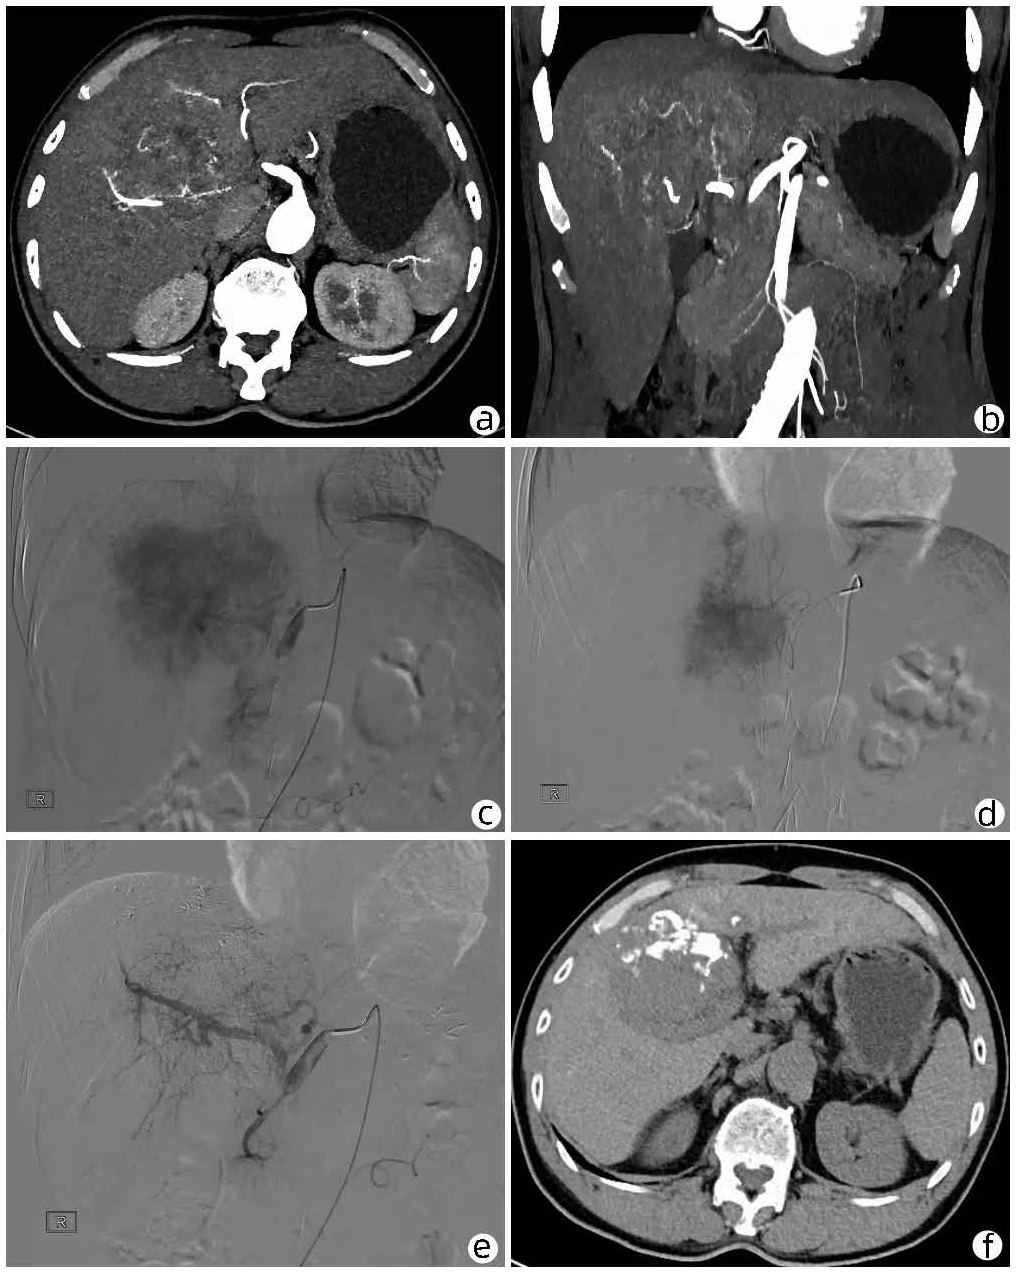

局部栓塞联合靶向免疫综合治疗肝肉瘤样癌1例报告

雷进, 张林枝, 陆荫英, 陈博文, 左石

2022, 38(4): 880-882. DOI: 10.3969/j.issn.1001-5256.2022.04.026

摘要(1323) HTML (453) PDF (3487KB)(82)

摘要: